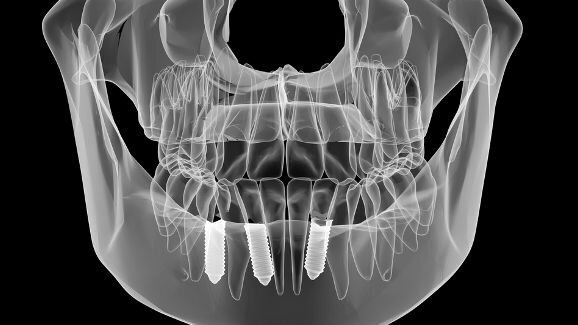

Високата прецизност при планирането и извършването на имплантологични процедури е важна за гарантирането на голям процент успеваемост. За да постигнат добри функционални и естетични резултати, много клиницисти използват хирургични шаблони за направляване на поставянето на импланта по време на операция. Наскоро китайски изследователи са направили оценка на ефекта на хирургичните шаблони върху точността при поставянето на имплантите и са установили значително разминаване между реалните и планираните имплантни позиции.

Според учените грешките в компютърно направляваната имплантна хирургия могат да бъдат приписани или на опериращия по време на операцията, или предоперативно на хирургичния шаблон. За да се оцени ефектът на шаблоните върху точността при поставянето на имплантите, са сканирани челюстите на 16 пациенти посредством конично-лъчева компютърна томография (CBCT). Във виртуална 3D среда са планирани 53 импланта, от които 35 са поставени мандибуларно и 18 максиларно.

За анализите е създаден стереолитографски хирургичен шаблон, който след това е поставен върху гипсов модел и сканиран със CBCT устройство. Получените изображения са сравнени с тези от виртуално планираните имплантни позиции. Реалните позиции на имплантите са получени от регистрираната позиция на хирургичния шаблон.

При сравнението на данните изследователите установили значителни отклонения между реалната и планираната позиция, дължащи се на хирургичните шаблони. Средното централно отклонение в хекса и апекса е било съответно 0.456 мм и 0.515 мм. Средното хоризонтално отклонение в хекса е било 0.193 мм, а в апекса 0.277 мм. Средното вертикално отклонение в хекса е било 0.388 мм, а в апекса 0.390 мм. Средното отклонение в ъглите е било 0.621°.

Резултатите от проучването предполагат, че клиницистите не трябва да разчитат единствено на безопасността на хирургичните шаблони, за да избегнат критичните анатомични структури.

Проучването, озаглавено „Влиянието на хирургичните шаблони върху точността при поставянето на импланти“, е публикувано онлайн на 30 ноември в сп. Journal of Prosthodontics. То е проведено от изследователи от Zhejiang University of Technology съвместно с Zhejiang People’s Hospital в Ханджоу, Китай.